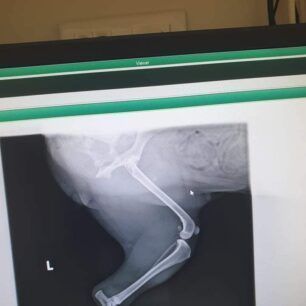

Το ζώο χειρουργήθηκε στις 9 Νοεμβρίου καθώς μεταξύ άλλων είχε και πυομήτρα. Οι ακτινογραφίες, που έβγαλε στην κλινική έδειξαν και τα πολλά σκάγια στο κορμί του – δηλαδή έχει πυροβοληθεί από κυνηγό – καθώς και το κάταγμα κνήμης και περόνης στο πόδι, το οποίο αντιμετωπίστηκε με νάρθηκα, αλλά και ο υγρό στον πνεύμονα (το όποιο αφαιρέθηκε με παρακέντηση). Είχε επίσης και εσωτερική αιμορραγία στην κοιλιακή χώρα.